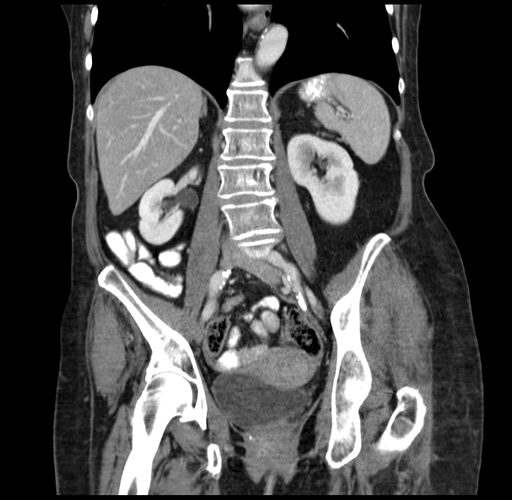

Coronal Venous